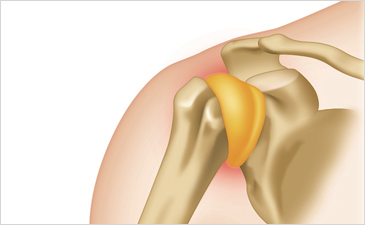

오십견(유착성관절낭염)이란?

오십견(유착성관절낭염)이란 어깨 관절을 감싸고 있는 관절낭이 두꺼워져 어깨 관절과 달라붙고, 달라붙은 부위에 염증과 통증이 나타나 관절의 움직임을 제한하는 질환입니다. 회전근개파열, 어깨충돌증후군과 함께 대표적인 어깨관절질환으로 어깨가 마치 얼어버린 것처럼 굳는다고 해서 ‘동결견’이라고도 불리며, 움직임이 적고 혈액순환이 잘 되지 않는 겨울철에 많이 나타나고 야간에 통증이 심해지기도 합니다. 보통 50세 전후에 많이 생긴다고 해서 오십견이라 불리지만 최근에는 삼십견, 사십견이란 말이 생길 정도로 발병연령층이 낮아지고 있습니다.